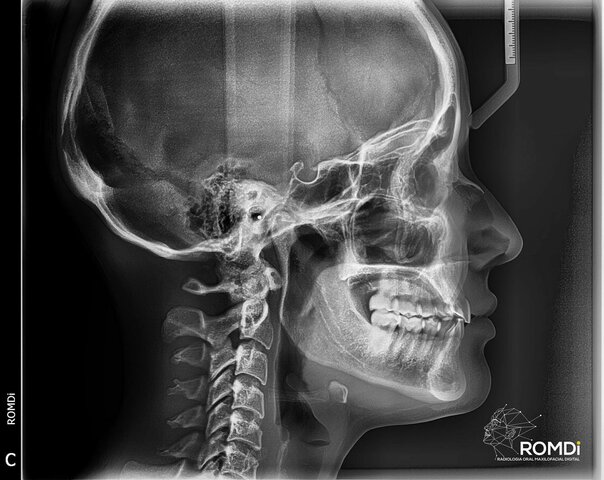

creación de los Rx en Odontología

• 1era Rx de Torax in situ

1era Rx de Torax in situ

Fue hecha por el escocés John MacIntyre, con un tiempo de exposición de 60 minutos y radiografías bastante

borrosas.